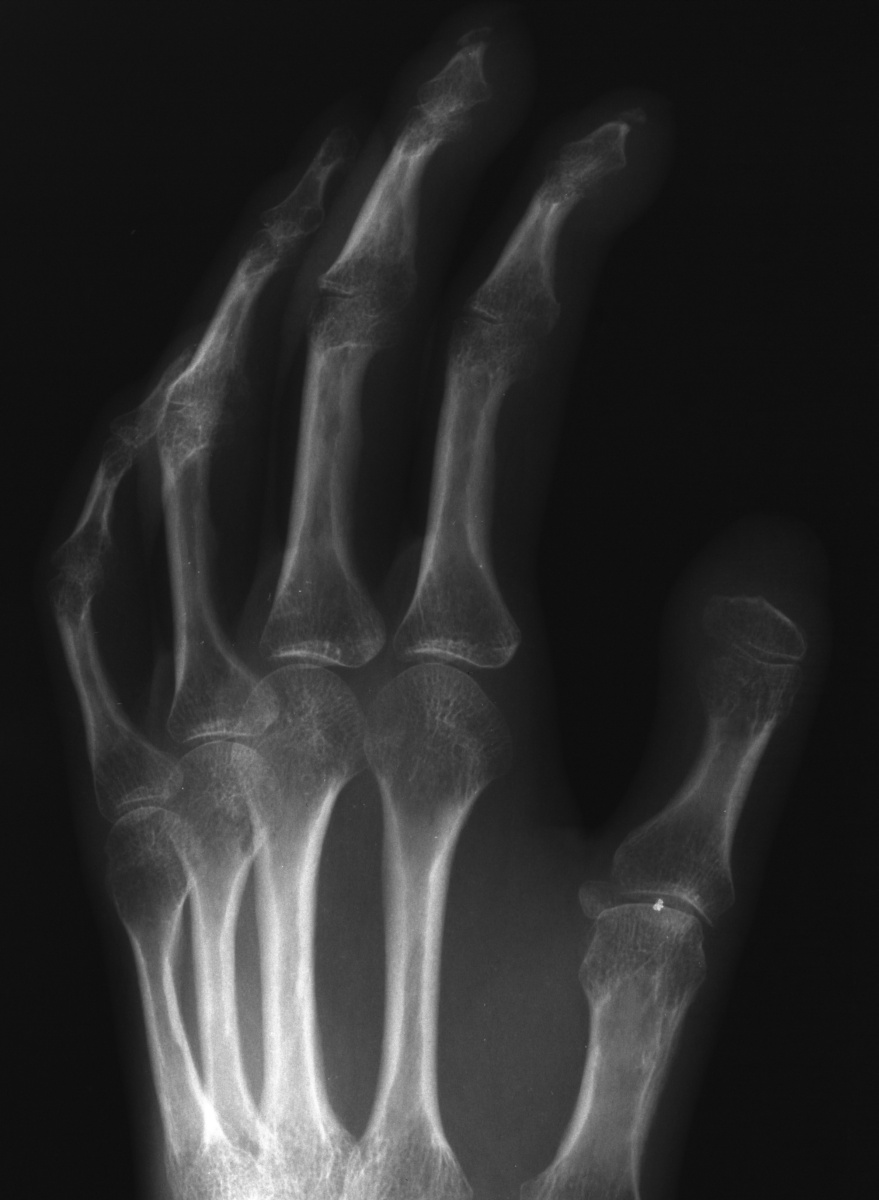

Clinical Example: Scleroderma, Calcinosis and Acroosteolysis

Scleroderma is a polymorphic condition , variably associated with a variety of conditions including joint stiffness, subcutaneous calcification and acroosteolysis. This patient with scleroderma demonstrates all of these conditions. This is most commonly associated with the finding of anticentromere antibodies.